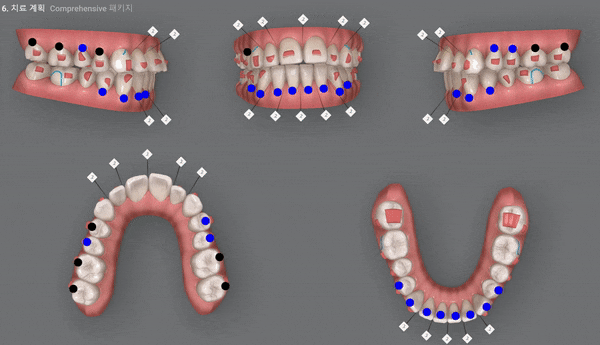

환자분께서는 인비절라인의 Comprehensive Package로

5년동안 재스캔하여 원하는 만큼 장치를 받아 인비절라인의 추가제작이 가능하시답니다.

두번째 클린체크

29개의 인비절라인 장치 완료 후 치아상태, 개방교합 개선됨

Final ClinCheck

두번째 클린체크는 11개의 장치를 통해 클린체크를 마무리 했습니다.

첫번째 클린체크에 이어 좀더 디테일한 부분까지 어금니 교합과 앞니 배열등 미세한 부분을 상호 보완, 개선하여 교정치료를 마무리 하셨는데요.

전체적으로 위 아랫니의 교합이 제 위치를 찾으며 정중선이 일치하도록 마무리를 해드렸습니다.